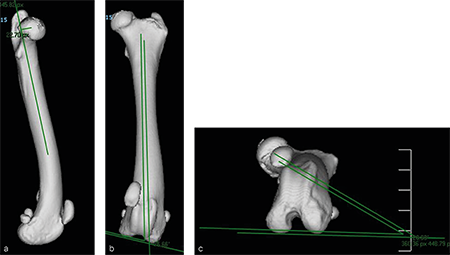

A 4-year- and 6-month-old spayed female mixed breed dog weighing 25.1 kg presented for chronic progressive left pelvic limb lameness. Orthopedic examination and preoperative x-rays revealed a grade 3/4 medial patellar luxation without concurrent cranial cruciate ligament rupture. A preoperative computed tomography (CT) was performed to screen for femoral varus and/or femoral torsion. Femoral varus was documented (anatomical Lateral Distal Femoral Angle [aLDFA] 104, normal 92-96). The femoral torsion angle was 26 and was like the unaffected contralateral limb and within the normal range. The planned correction was a 12 lateral closing wedge ostectomy, with concurrent sulcoplasty and tibial tuberosity transposition. The mediolateral view of the preoperative CT 3D reconstruction of the left femur (Fig 5a) illustrates anatomical anteversion of the femoral head and neck and procurvatum of the femur, and the craniocaudal view (Fig 5b) confirms distal femoral varus (anatomical Lateral Distal Femoral Angle, 104).